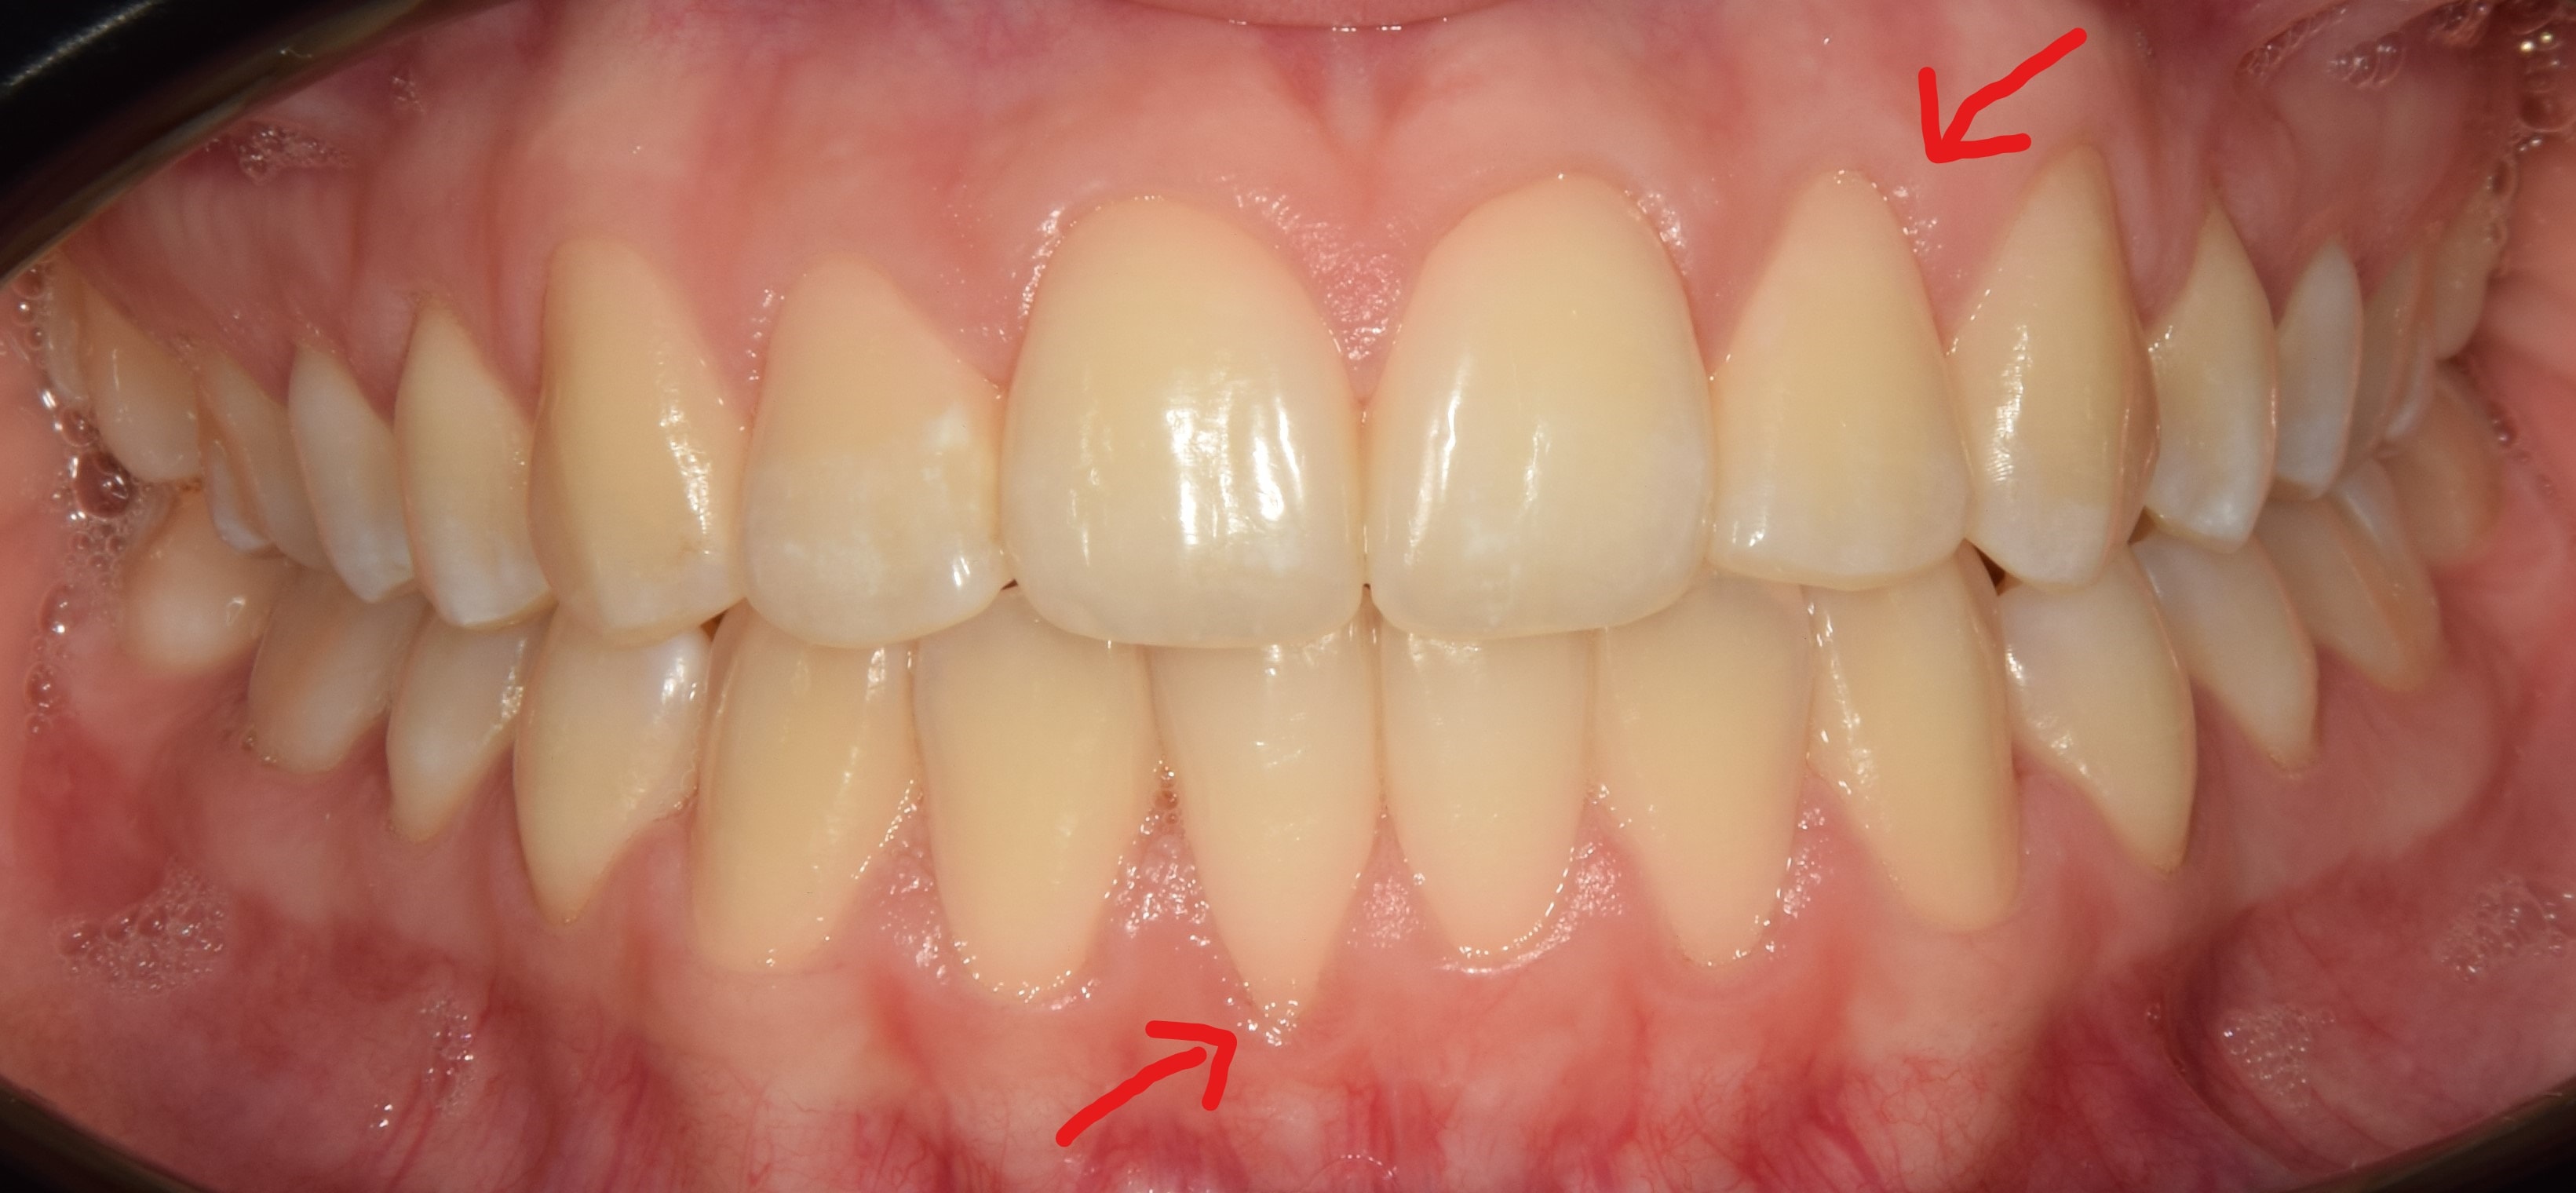

Ínyvisszahúzódás

Abban az esetben, ha egy adott fog külső vagy belső oldalán valamilyen okból csontfelszívódás történik, úgy a csont szintjét követve sokszor az íny is visszahúzódik, szabaddá téve a fog külső vagy belső felszínét (fognyakat vagy akár foggyökeret is). Fontos megjegyezni, hogy ínyvisszahúzódás nem alakul ki tökéletes szájhigiéné mellett. Gyakran látott kórkép fogszabályozó kezelés előtt, melyet a fog helytelen pozíciója okoz, és a megfelelő mozgatásokkal korrigálható, visszafordítható. Számos esetben azonban éppen a fogszabályozó kezelés mellékhatásaként léphet fel ínyrecesszió, legtöbbször túlkompenzált esetekben. Parodontológus kollégák képesek kezelni az ínyrecessziót különböző technikák segítségével, így aggodalomra semmi ok. Fontos viszont, hogy a szabaddá vált fogfelszínt óvatosan, puha sörtéjű fogkefével tisztítsuk, másképp károsíthatjuk a fog keményszöveteit.